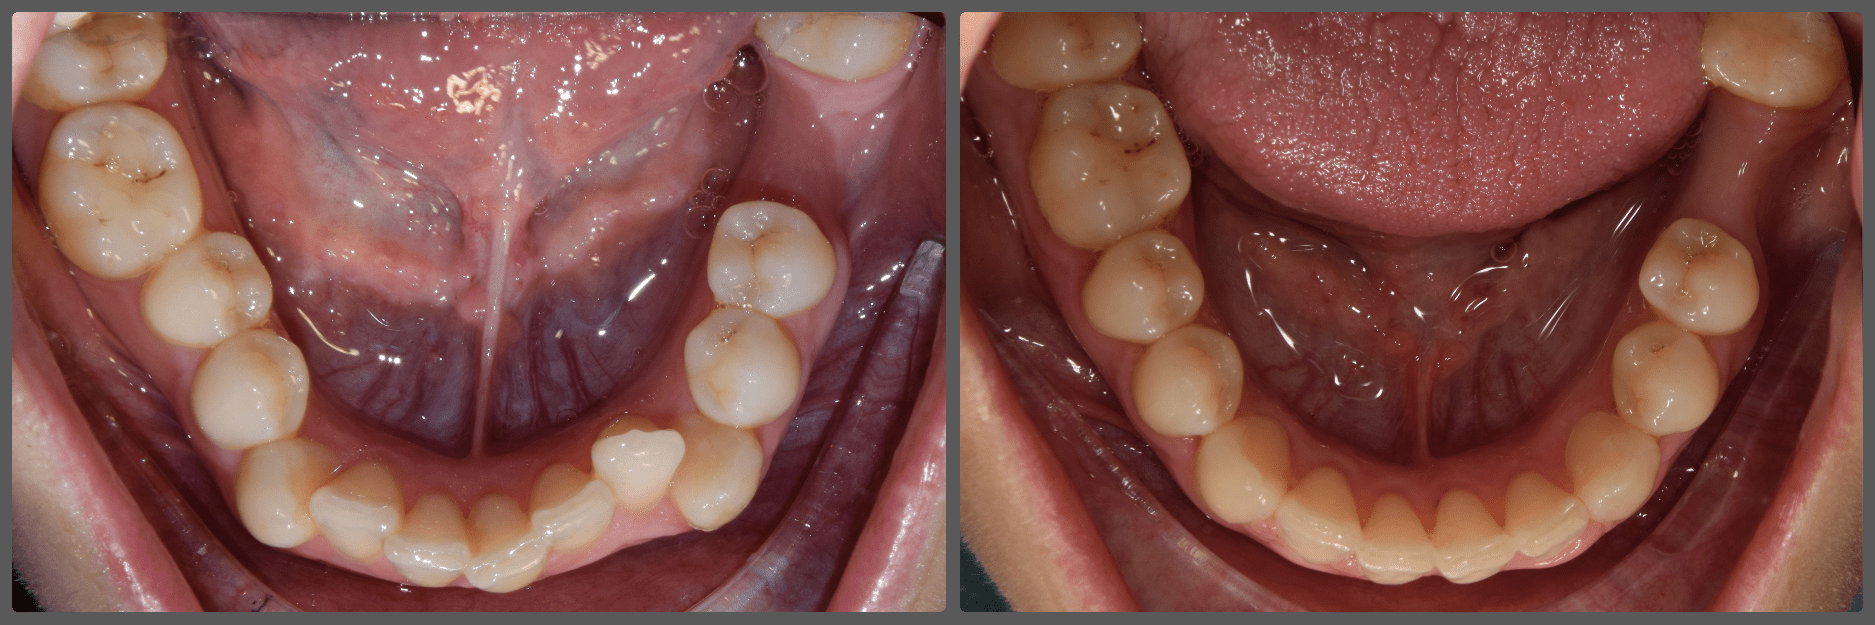

Zoli torlódott alsó fogai miatt szeretett volna fogszabályozó készüléket. Régebben 2 db felső kisőrlő fog eltávolításával már fogszabályozták, azonban az alsó fogív eltérései jelentősek voltak. A torlódás mellé közepes mértékű mélyharapás társult, valamint a bal oldali kisőrlő fogaknál non-occlusiot figyeltem meg. Ez azt jelenti, hogy esetünkben a felső első kisőrlő fog az alsó első és második kisőrlő fog közé, de azok külső felszínére harap. Ez a felső fogat kifelé, az alsókat befelé, a nyelv felé dönti és hosszútávon súlyos elváltozást okoz. Alsó-felső Pitts21 rögzített fogszabályzóval, intermaxilláris gumihúzással, harapásemelőkkel és tolórugókkal Zoli fogait nagyon gyorsan, 13 hónap alatt sikerült tökéletes pozícióba szabályoznunk, mind esztétikai, mind funkcionális szempontból (persze ehhez kellett a töretlen lelkesedése, együttműködése is). A kezelés végén az alsó fogívre fix retainert helyeztem fel az elért állapot megőrzésére. A végeredmény úgy gondolom mindent elmond!